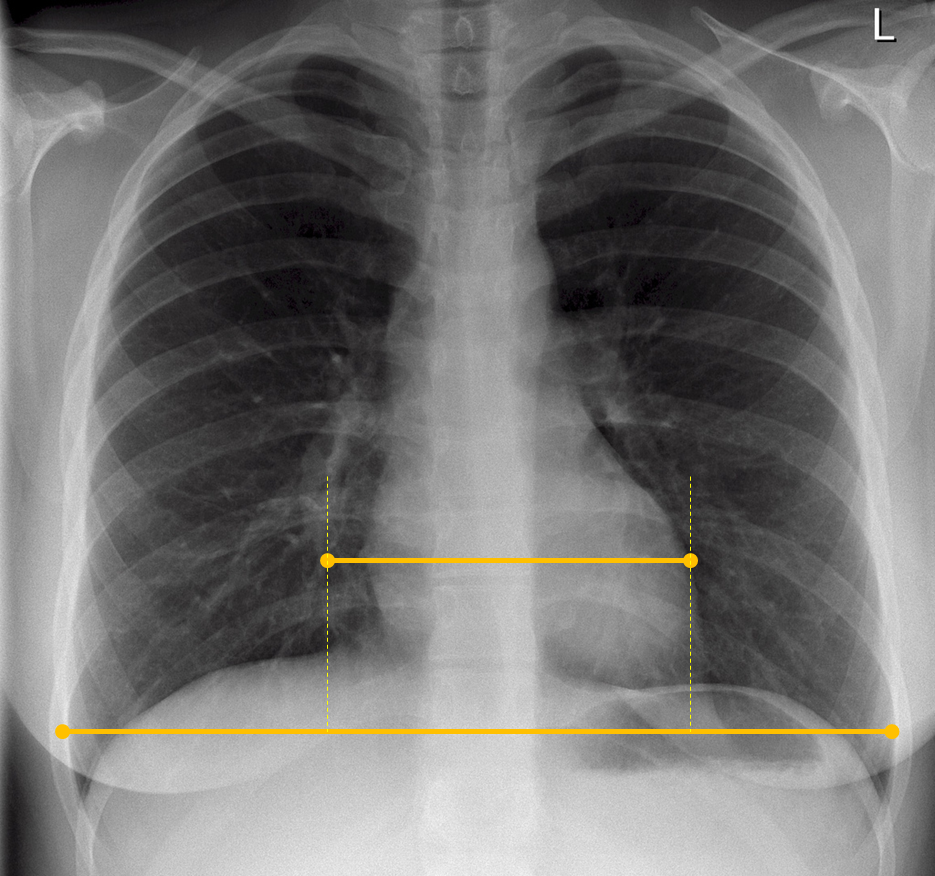

What should the cardio-thoraic ratio be?

Cardio-Thoracic Ratio (CTR) should be <50% on a PA (posterior-anterior i.e. back to front) image*

CTR- heart size should be half the width of the chest